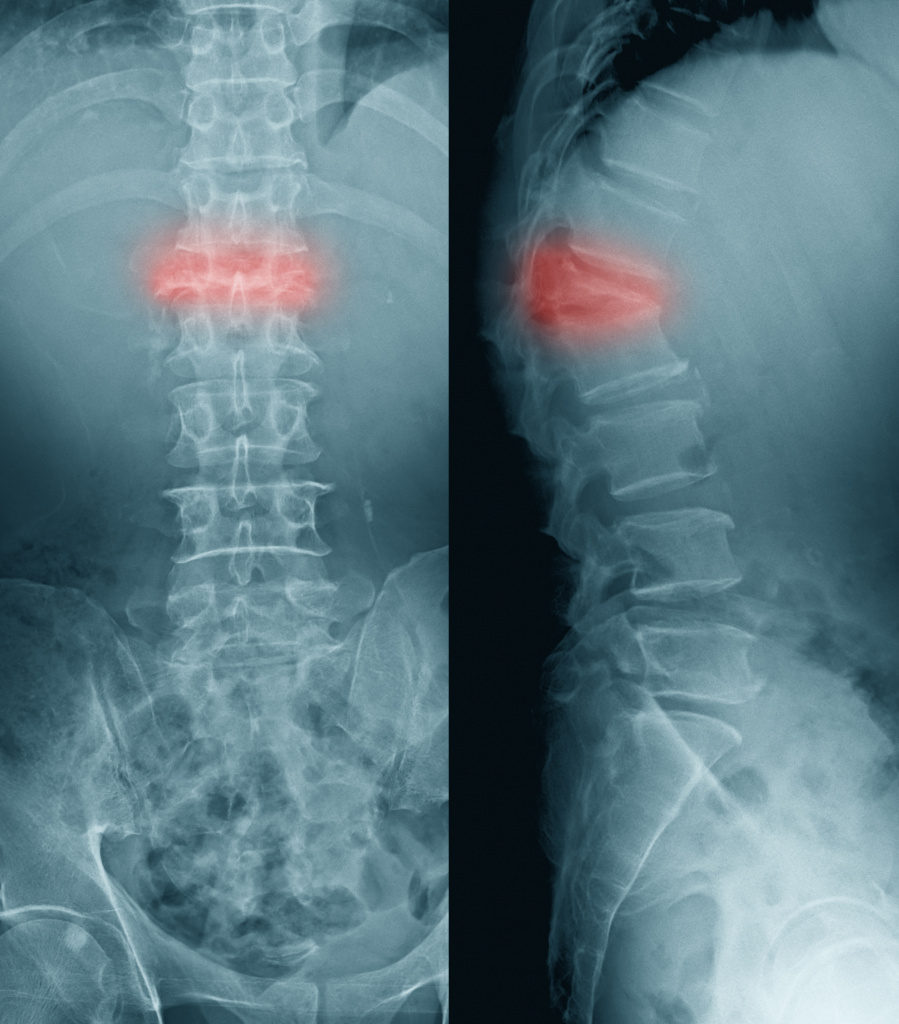

Рентгеновские снимки и медицинские изображения компрессионных переломов